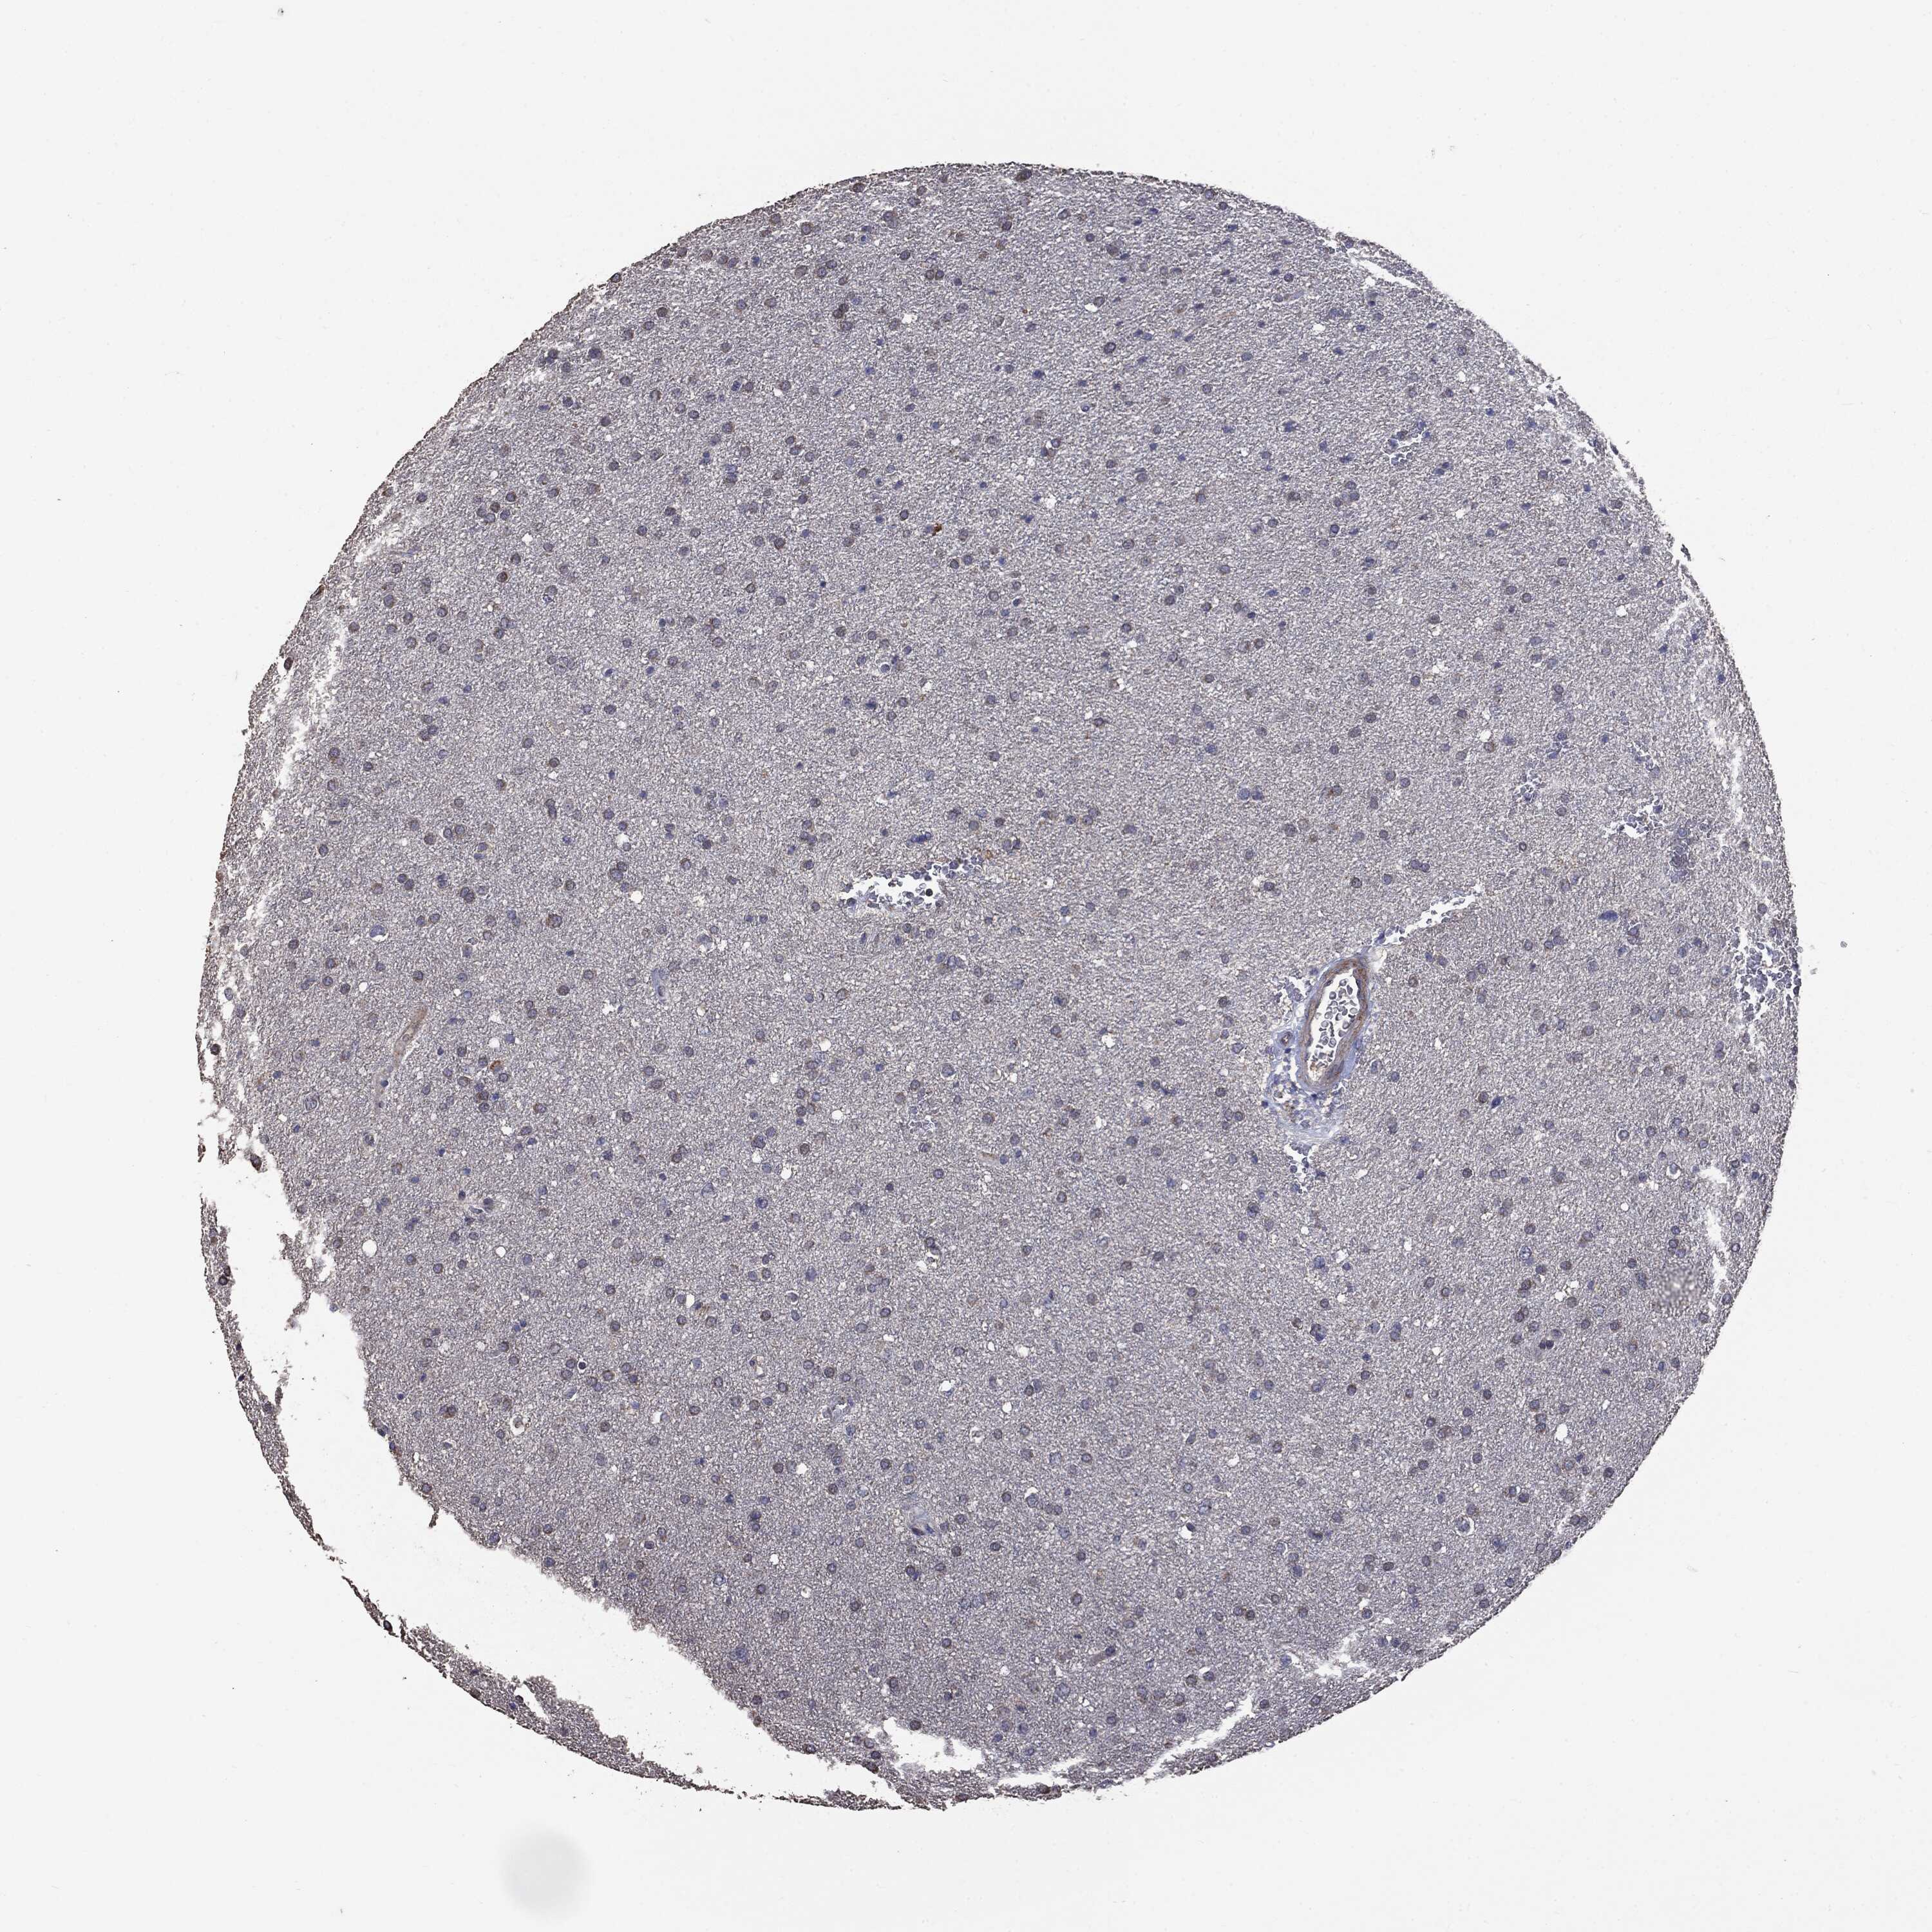

GLIOMA - Protein expressioni

A mouse-over function shows sample information and annotation data. Click on an image to view it in a full screen mode. Samples can be filtered based on level of antibody staining by selecting one or several of the following categories: high, medium, low and not detected. The assay and annotation is described here.

Note that samples used for immunohistochemistry by the Human Protein Atlas do not correspond to samples in the TCGA dataset.

Antibody stainingi

Antibody staining in the annotated cell types in the current human tissue is reported as not detected, low, medium, or high, based on conventional immunohistochemistry profiling in selected tissues. This score is based on the combination of the staining intensity and fraction of stained cells.

Each image is clickable and will lead to virtual microscopy that enables deeper exploration of all samples and also displays staining intensity scores, fraction scores and subcellular localization as well as patient and tissue information for each sample.

CAB069425

CAB080053

CAB080065

CAB080070

CAB080081

CAB080095

CAB080097

Staining

High

Medium

Low

Not detected

Intensity

Strong

Moderate

Weak

Negative

Quantity

>75%

75%-25%

<25%

None

Location

Nuclear

Cytoplasmic/membranous

Cytoplasmic/membranous,nuclear

Glioma, malignant, Low grade

Glioma, malignant, High grade

Glioma, malignant, NOS